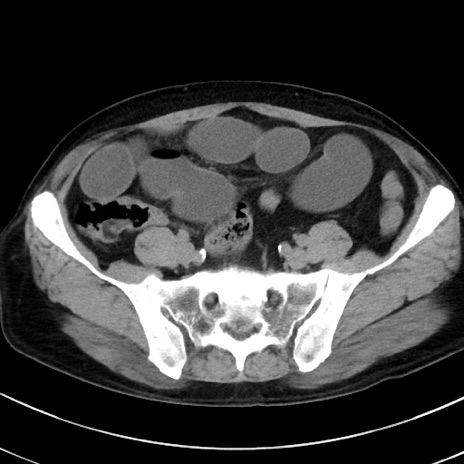

症例38(横断像)

【症例】70歳代 男性

【主訴】腹痛・嘔吐

【現病歴】昨晩より、嘔吐・腹痛あり。今朝になっても嘔吐あり。来院。

【既往歴】心臓バイパス手術、開腹胆摘、腸閉塞

【身体所見】BP 107/71mmHg、HR 116/min、腹部:平坦、軟、下腹部に軽度圧痛あり。反跳痛なし。

【データ】WBC 15100、CRP 0.32